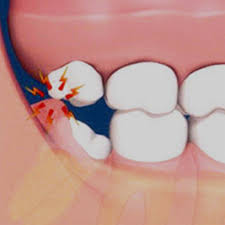

▶사랑니가 똑바로 나지 않고 비스듬히 난 경우 ▶사랑니 주변 잇몸이 자꾸 붓고 아픈 경우 ▶사랑니와 그 앞 어금니 사이에 음식물이 자주 끼는 경우 ▶사랑니에 충치가 생겼으나 치료가 어려운 경우 ▶사랑니 앞의 어금니를 치료해야 하는데 사랑니로 인해 정상적인 치료가 어려운 경우 ▶교정치료를 해야 하는데 사랑니가 방해가 되는 경우 ▶X선 검사 소견 상 사랑니 주변에 혹으로 의심할 만한 부분이 나타난 경우 사랑니를 반드시 빼야 한다고 한다.

한 대학병원 치과 교수는 “젊을 때 빼지 않아도 되는 사랑니라고 판정받았어도 나이가 들면서 사랑니를 빼야 하는 사례가 생긴다”며 “나이 들수록 잇몸뼈의 양이 줄어 사랑니가 뼈 밖으로 살짝 나오면서 주변 잇몸과 인접한 치아를 계속 자극해 통증과 충치를 유발한다”고 말했다고 한다.